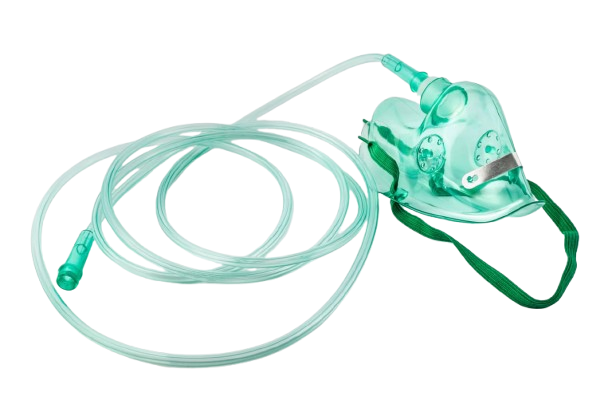

Oxygen Mask

Oxygen MaskOur ProductsFrom SurgicaveUplode:9 months ago from India